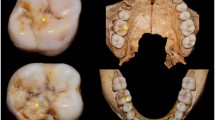

Raman spectroscopy was used to investigate how the effect of pre-treatment protocols, with combinations of hydrochloric acid (HCl), sodium hypochlorite (NaOCl) and hydrogen peroxide (H2O2), for molar–incisor hypo-mineralisation (MIH) altered the penetration depth of polymer infiltrants (ICON, DMG, Hamburg, Germany). Furthermore, the effect on the structure of the MIH portions of the teeth with treatment is examined using multivariate analysis of spectra. It was found that pre-treatment protocols improved penetration depths. The structure of the MIH portion post-treatment appeared much closer to that of normal enamel suggesting a diminution of protein in the MIH region with treatment.

Fraser SJ, Natarajan AK, Clark ASS, Drummond BK, Gordon KC (2015) A Raman spectroscopic study of teeth affected with molar-incisor hypomineralisation. J Raman Spectrosc 46(2):202–210. doi:10.1002/jrs.4635

Crombie F, Manton D, Palamara J, Reynolds E (2014) Resin infiltration of developmentally hypomineralised enamel. Int J Paediatr Dent 24(1):51–55

Paris SA, Dorfer CE, Noren JG, Meyer-Lueckel H (2013) Resin infiltration of hypomineralised enamel in MIH-molars. Paper presented at the IADR General Session, Seattle, Washington